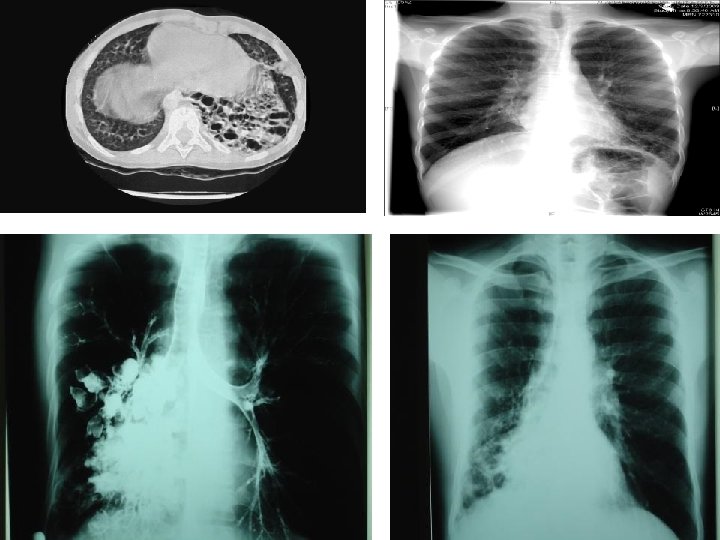

Left bronchus syndrome , Next slide Plzzz =) Notice , the Trachea is pulled to left side. . WHY ? cuz of fibrosis there is loss of space , loss of ventilation in the left side , the left lung is smaller in size , infective , bronchioectatic , it will pull the trachea toward it.

Left bronchus syndrome : Chronic condition , it is the end sequelae ﺍﻟﻨﺘﻴﺠﺔ ﺍﻟﻨﻬﺎﺋﻴﺔ of lung destruction due to TB In the previous slide , notice the bronchioectatic changes all over the lung ! Rt lung : pt still can breath from it , although it has apical scarring , Rt upper zone infiltration. Lt Lung : has Abcess cavity , Air Fluid levels , cystic bronchiectasis. If we did bronchoscopy , bronchoalveolar lavage , we will see the Fast Bacilli of Mycobacterium TB , which are resistant to 1 st , 2 nd and 3 rd line anti-TB medications ! ﻧﺘﻴﺠﺔ ﺑﺆﺮﺓ ﺍﻟﺘﻬﺎﺑﻴﺔ Left bronchus syndrome : The study was done at KKUH , if u r interested : http: //www. ncbi. nlm. nih. gov/pmc/articles/PMC 462386/pdf/thorax 00339 -0050. pdf 0